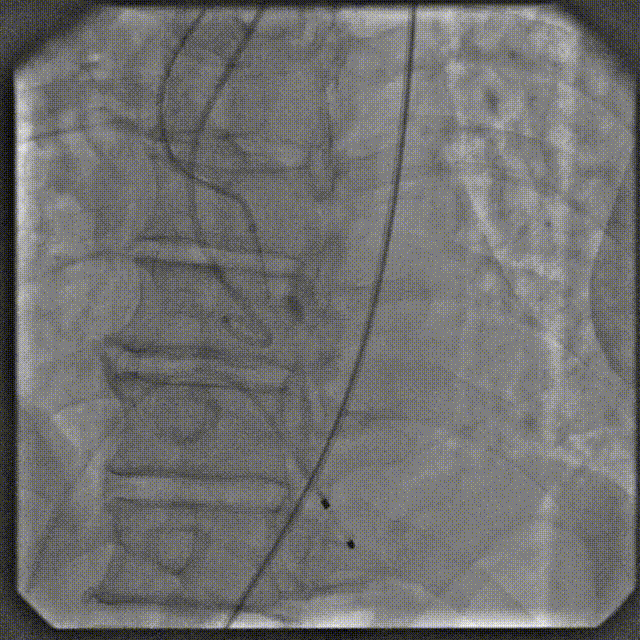

在数字减影血管造影(DSA)与经胸超声(TTE)双模影像引导下,学员系统完成经导管主动脉瓣置换术全流程操作:首先建立经皮腹主动脉穿刺入路,随后进行导丝跨瓣定位,继而操控人工瓣膜输送系统,最终实现瓣膜精准释放。训练重点强化三个技术维度:①血管入路建立与并发症预防 ②影像引导下的器械递送路径规划 ③基于实时超声的血流动力学评估。